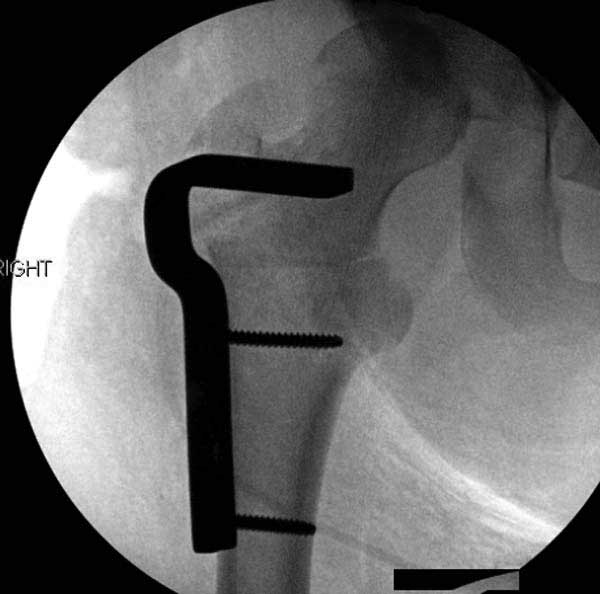

Первым этапом сделана подготовка к ротационной межвертельной остеотомии, затем капсулотомия с удалением импинджмента и периацетабулярная остеотомия с 40 градусной экстензией и операция закончена 35 градусной наружной ротацией бедра. Запланированный варус не сделан из-за относительно нормального покрытия головки.

Одним из преимуществ ПАО является сохранение задней колонны, и всю фиксацию в основном делают спереди из крыла подвздошной кости. При реконструкционных операциях по поводу дисплазии редко коррекция превышает 25 градусов, и достаточной бывает фиксация тремя шурупами вертикально сверху вниз, и один между колоннами спереди кзади. Но у нашего пациента серьезные изменения, и для достижения результата надо было около 40 градусов коррекции, из-за чего в линии остеотомии создалась ступенька. Для предупреждения скольжения дополнительно установлена buttress пластина, которая зафиксирована только в одном сегменте, а другие два шурупа удерживают ASIS. Без остеотомии Anterior Superior Iliac Spine невозможен доступ внутри таза.